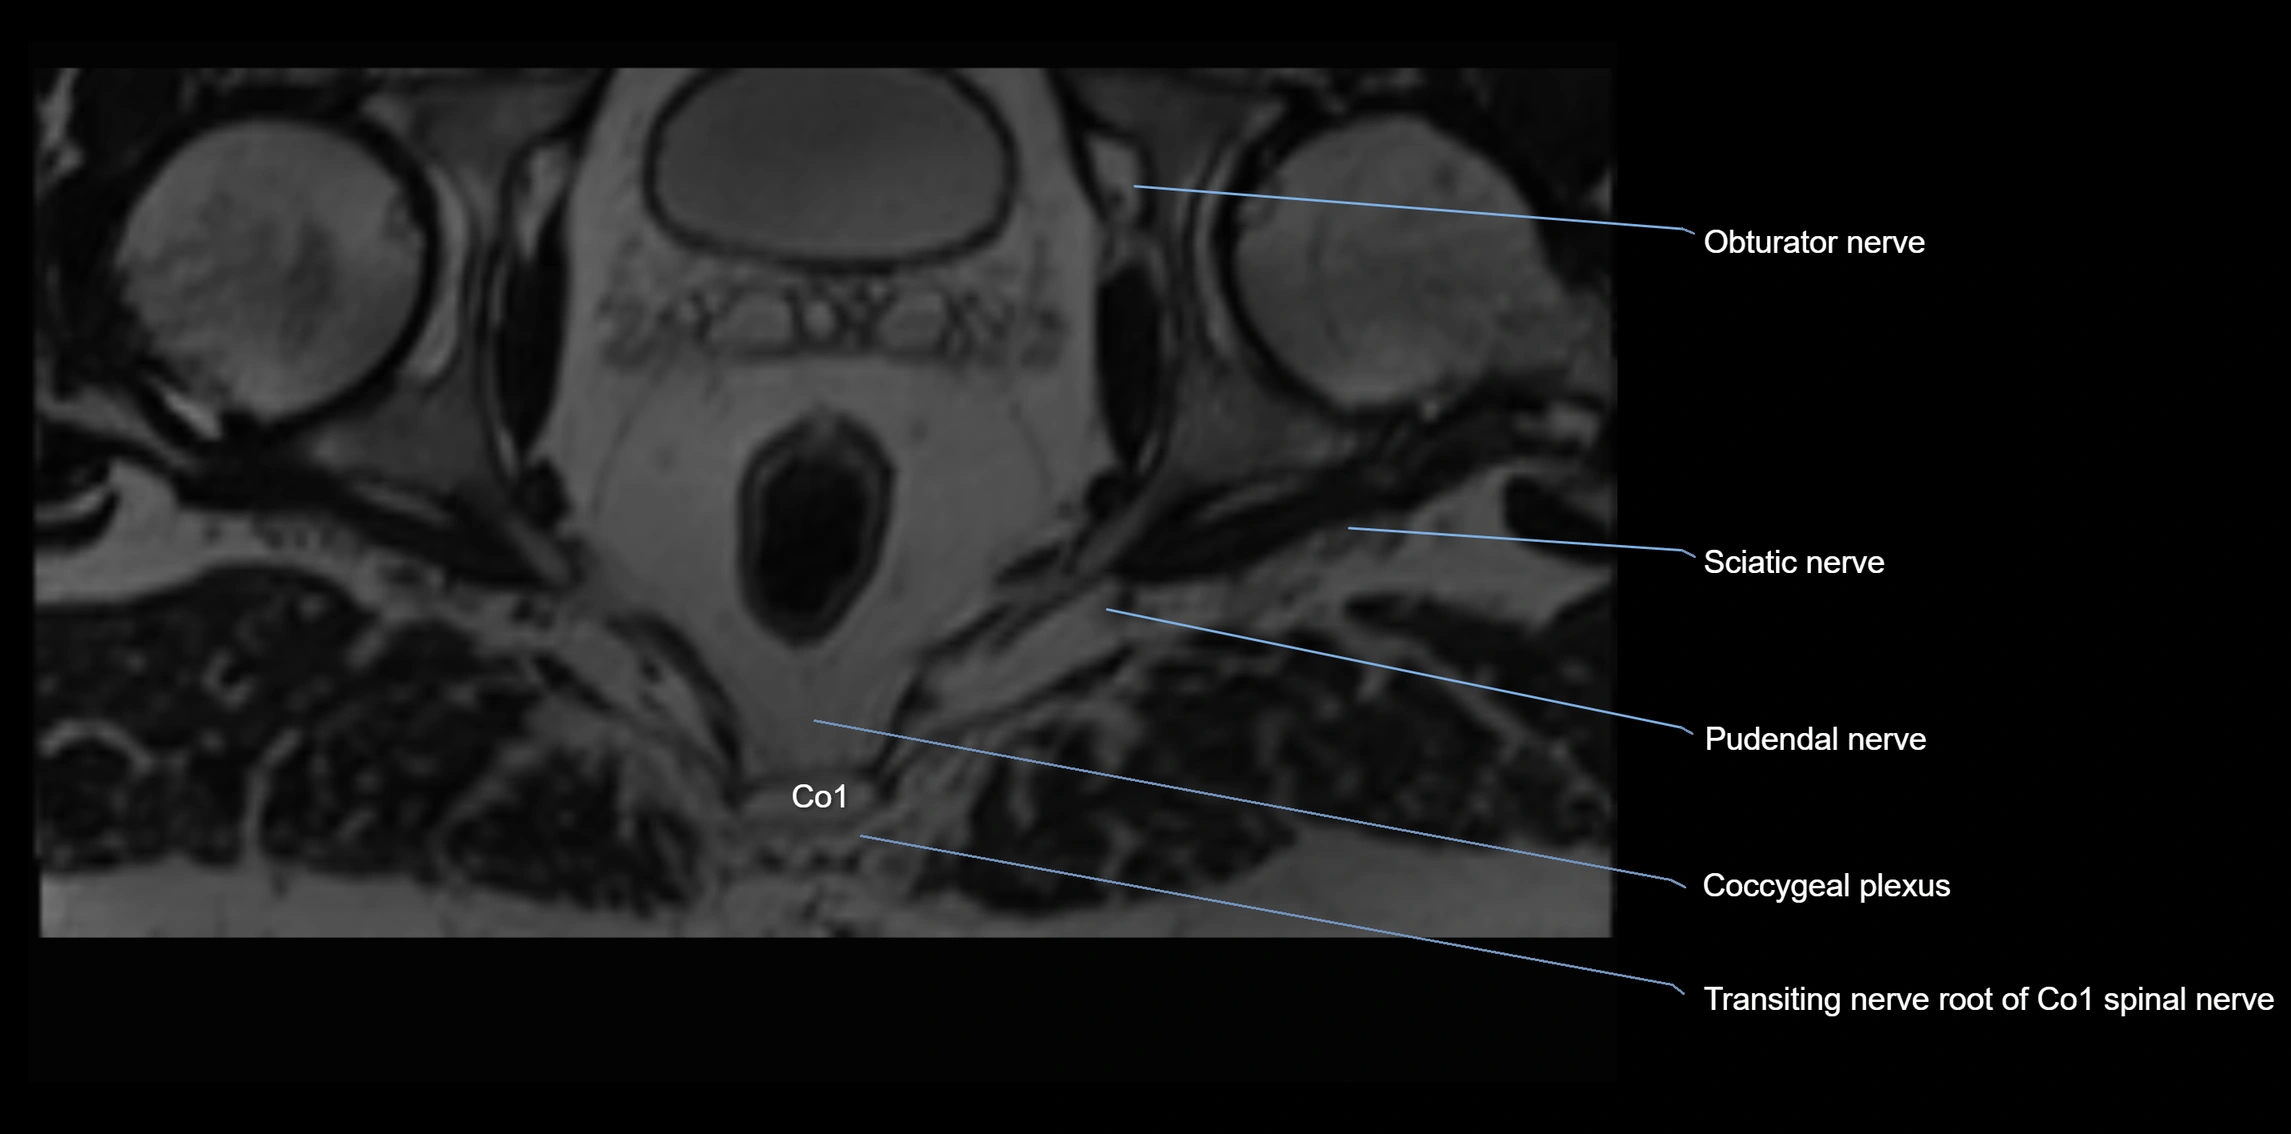

MRI Appearance

T1-weighted images:

• Nerve appears as a very thin low-to-intermediate signal intensity structure

• Surrounded by bright fat, aiding visualization

T2-weighted images:

• Nerve shows intermediate to mildly hyperintense signal compared to muscle

• Pathological involvement appears brighter

STIR (Short Tau Inversion Recovery):

• Normal nerve appears dark

• Inflamed or entrapped nerve appears bright hyperintense

T1 Fat-Sat Post-Contrast:

• Normal nerve enhances minimally

• Pathologic nerve (neuritis, entrapment, tumor infiltration) shows focal or diffuse enhancement

3D T2 SPACE / CISS:

• Nerve appears intermediate to mildly hyperintense compared to muscle

• Surrounded by bright fat or CSF, improving visualization

• Best sequence for mapping small pelvic nerves such as the anococcygeal

MRI image

image